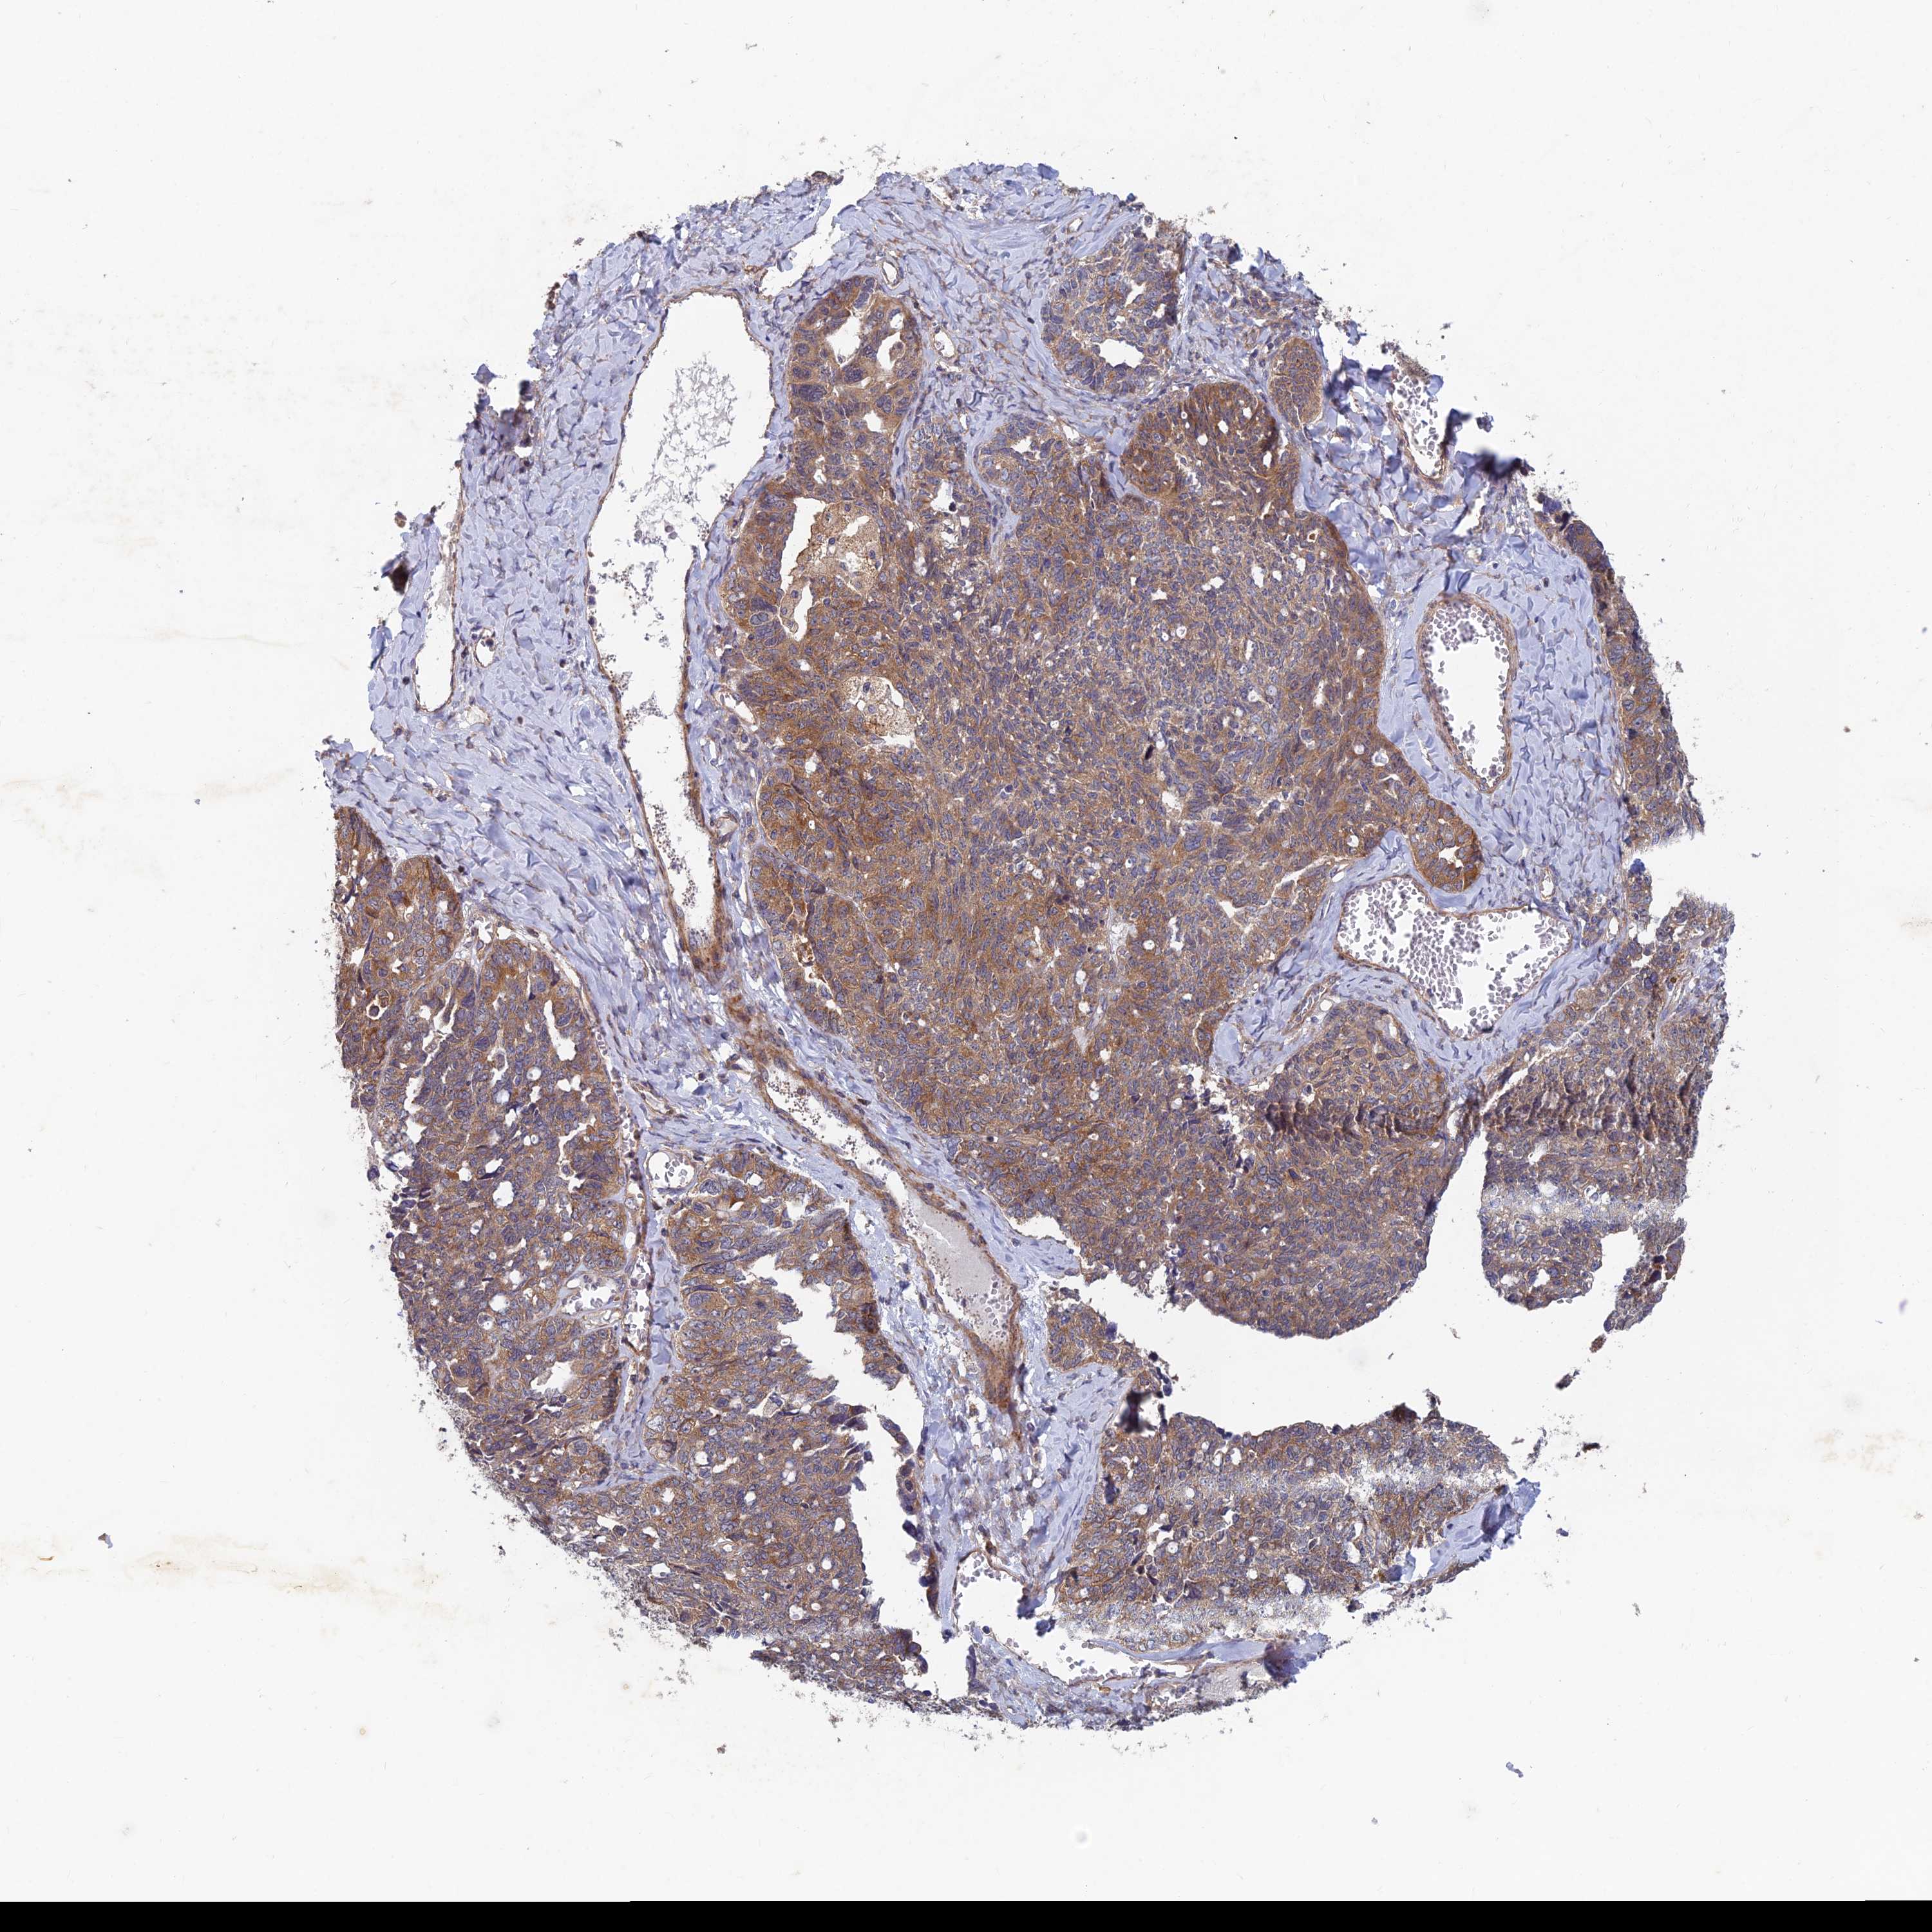

OVARIAN CANCER - Protein expressioni

A mouse-over function shows sample information and annotation data. Click on an image to view it in a full screen mode. Samples can be filtered based on level of antibody staining by selecting one or several of the following categories: high, medium, low and not detected. The assay and annotation is described here.

Note that samples used for immunohistochemistry by the Human Protein Atlas do not correspond to samples in the TCGA dataset.

Antibody stainingi

Antibody staining in the annotated cell types in the current human tissue is reported as not detected, low, medium, or high, based on conventional immunohistochemistry profiling in selected tissues. This score is based on the combination of the staining intensity and fraction of stained cells.

Each image is clickable and will lead to virtual microscopy that enables deeper exploration of all samples and also displays staining intensity scores, fraction scores and subcellular localization as well as patient and tissue information for each sample.

Antibody HPA039613

Staining

High

Medium

Low

Not detected

Intensity

Strong

Moderate

Weak

Negative

Quantity

>75%

75%-25%

<25%

None

Location

Nuclear

Cytoplasmic/membranous

Cytoplasmic/membranous,nuclear

Cystadenocarcinoma, serous, NOS

Carcinoma, endometroid

Cystadenocarcinoma, mucinous, NOS

Carcinoma, NOS